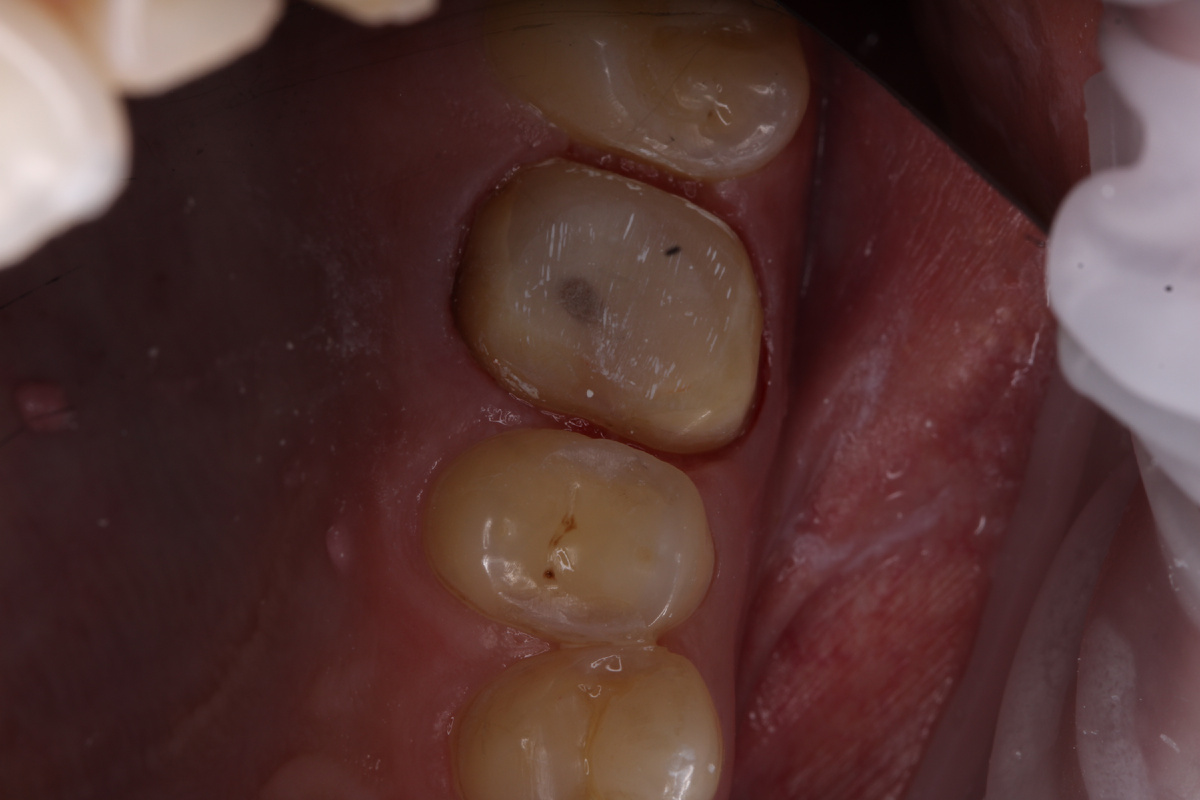

ИСКУССТВЕННАЯ КОРОНКА

В данном случае ко мне пришел пациент с обширной композитной реставрацией. Чтобы защитить зуб нужно изготовить коронку. Используемый материал - диоксид циркония.

Так выглядит зуб после препарирования: